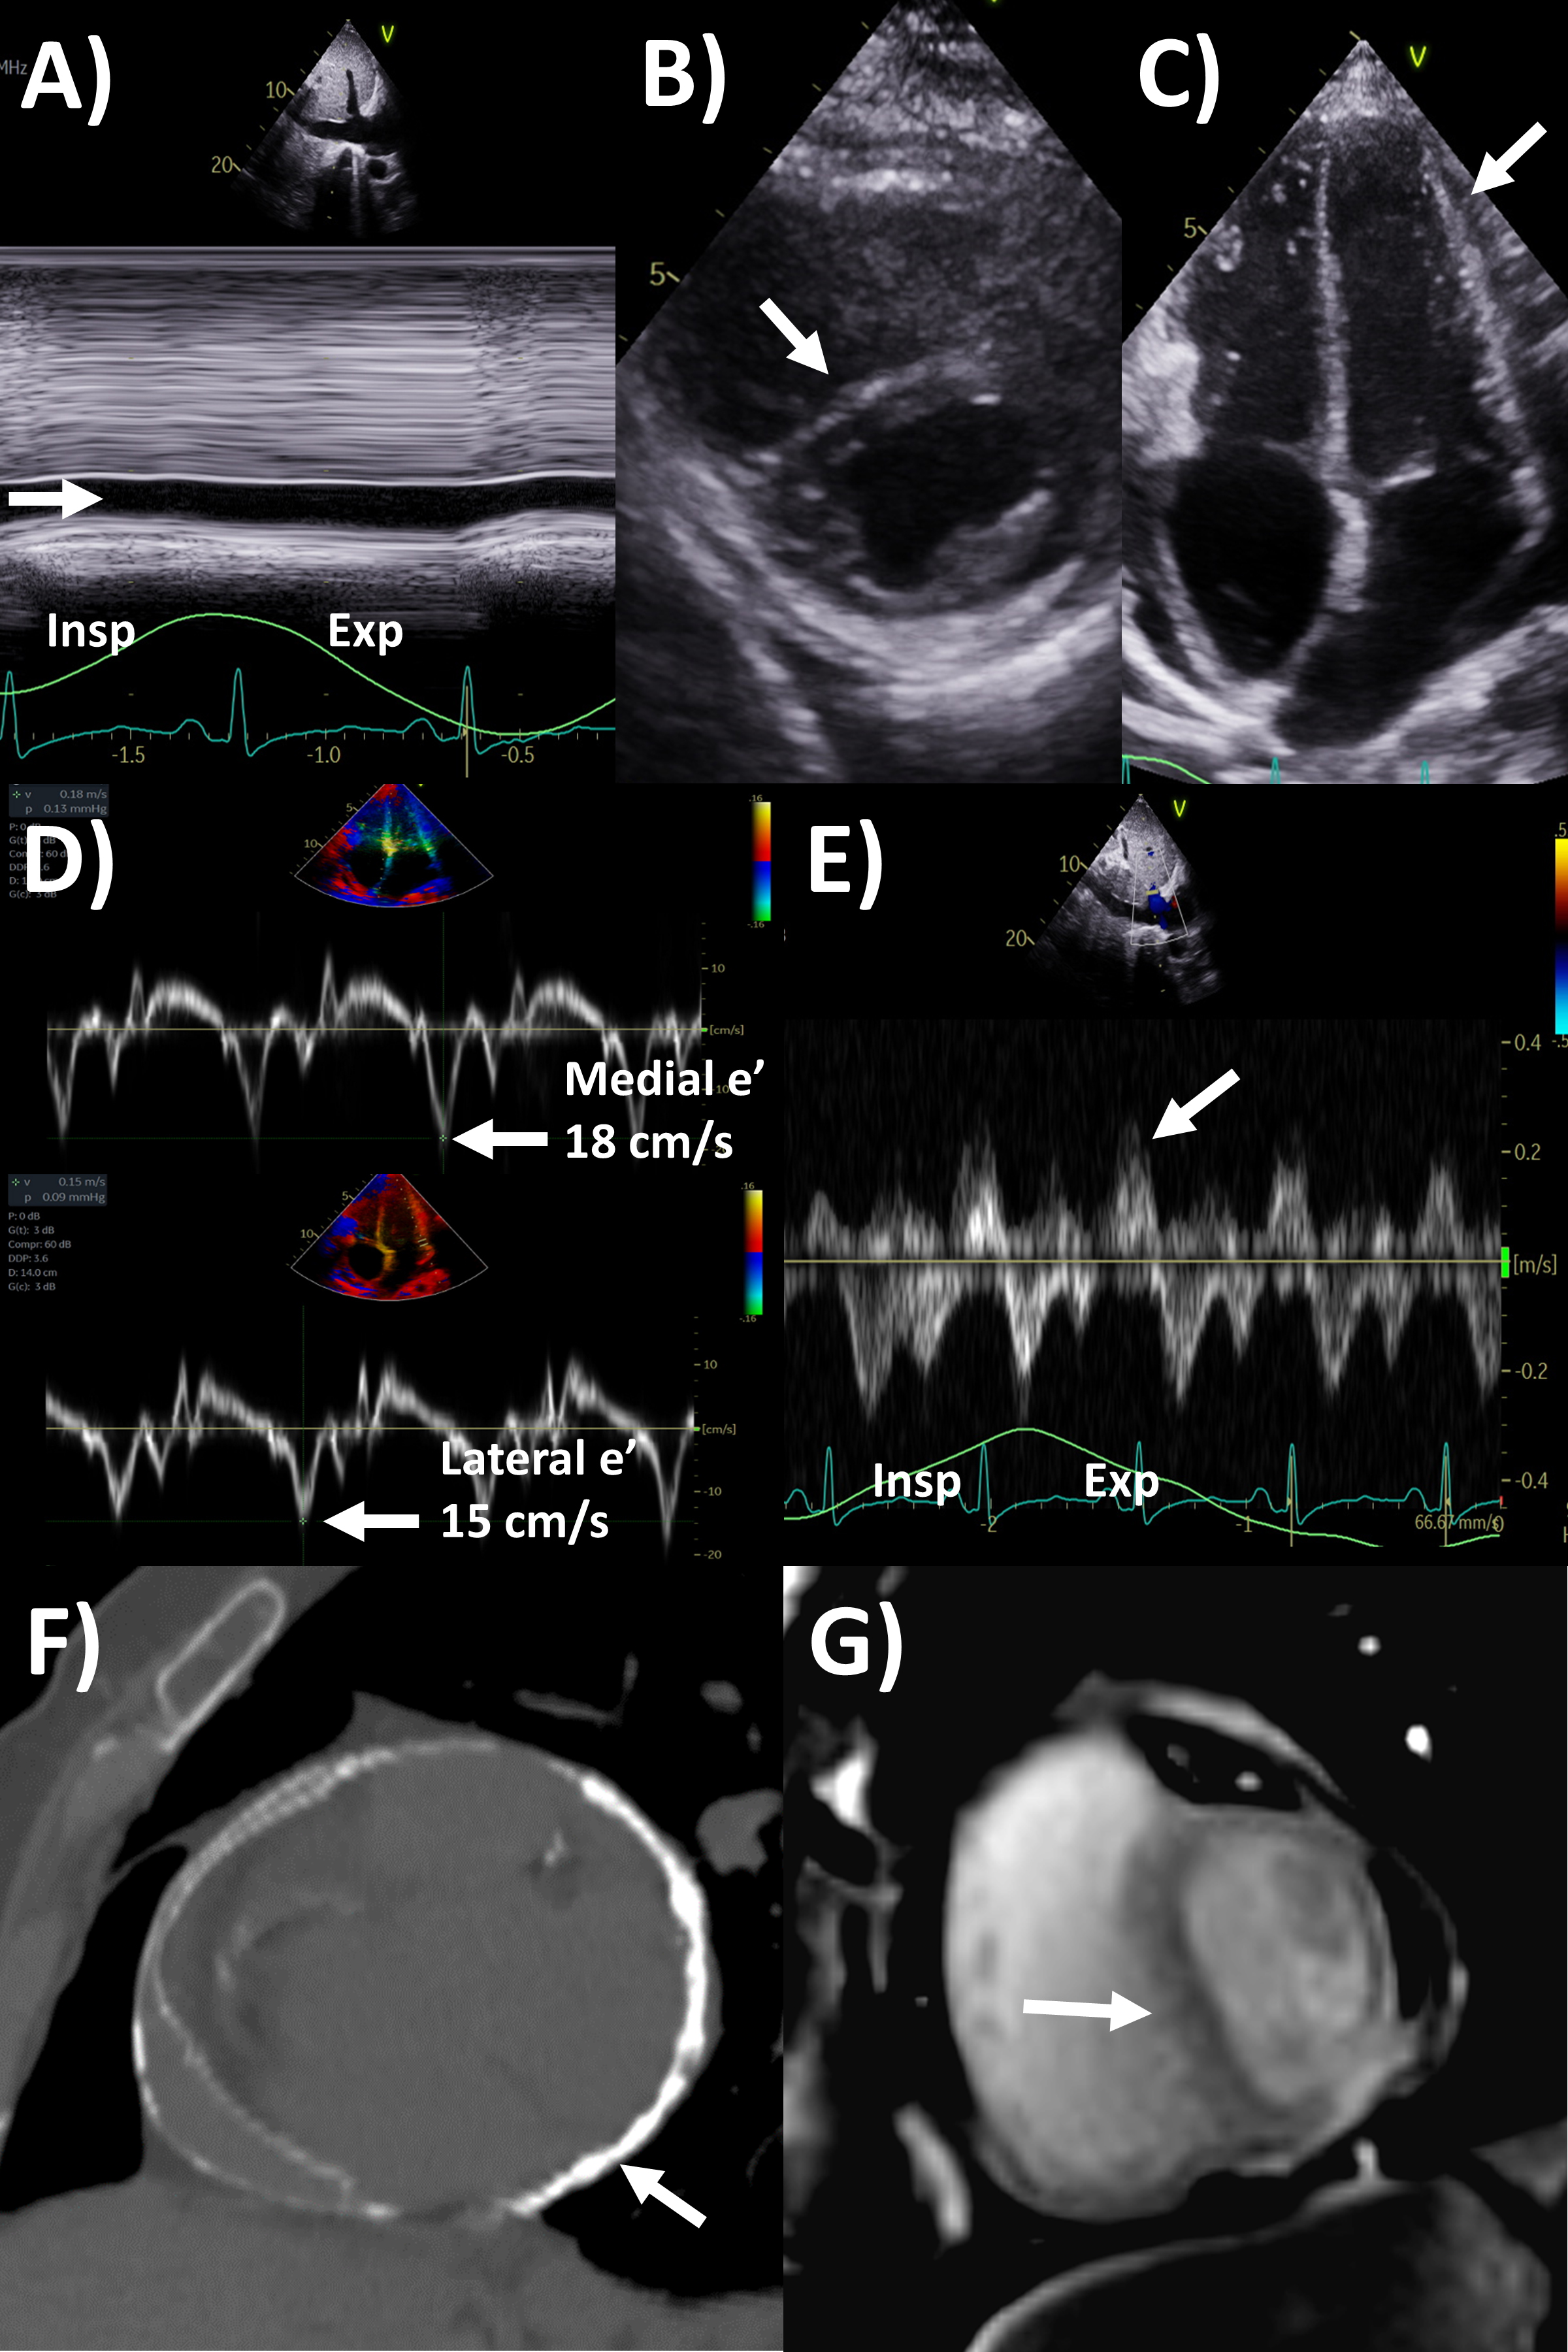

CT has greater ability for tissue characterization than echocardiography, and is able to assess the extent, local or distant spread of masses, lymph node involvement and many pericardial tumors have associated effusions that are hemorrhagic or exudative [31]. Hemangiomas appear heterogenous with contrast enhancement; lymphangiomas are heterogenous with low attenuation and septae; lipoma have low fat-level attenuation that is circumscribed, and sometimes can surround coronary arteries; teratomas usually have contain areas of calcification and fat; lymphoma are hypoattenuating with contrast enhancement; fibromas are homogeneous with no or minimal enhancement given lack of vascularity; sarcomas are broad-based masses which invade adjacent structures; and mesothelioma is seen as diffuse irregular pericardial thickening with effusion [31, 56]. Pericardial cysts are seen as a well-circumscribed homogeneous mass with thin wall on CT, with fluid density, unaffected by intravenous contrast (Fig. 4) [59, 60].

Fig. 4.Multi-modality imaging tissue characterization of pericardial cyst (arrows in all panels) adjacent to the right atrium. (A) Computed tomography axial slice, cyst was 10 Hounsfield units. (B) Magnetic resonance imaging (MRI) steady-state free precession bright blood sequence axial slice, cyst has increased signal. (C) MRI T2-short tau inversion recovery sequence, cyst has high signal. (D) MRI late gadolinium enhancement sequence axial slice, cyst has low signal.

MRI’s main advantage amongst imaging modalities is its ability in tissue characterization, and this is no different when applied to pericardial masses. Depending on tumor extension, the pericardium or myocardium may show thickening, or pericardial effusions, the latter often exudative or hemorrhagic with high signal intensity on T1-weighted sequences [31]. On T1-weighted, T2-weighted and gadolinium enhanced sequences, many tumors have low, high and high signal intensities [14, 31, 61, 62, 63]. Hemangiomas generally appear heterogeneous on all sequences, while lipomas have high signal intensity on all sequences, however its signal can be uniquely suppressed on fat-saturation pulse sequences. Fibroma have low vascularity and therefore have low signal intensity on T2-weighted sequence and none to minimal enhancement on gadolinium enhanced sequences. Mesotheliomas appear homogeneous on T1-weighted but have heterogenenous elevated signal on T2-weighte and gadolinium enhanced sequences. Of note, some studies have suggested heterogenous gadolinium uptake to indicate areas of increased lesion nodularity, growth and/or necrosis [64]. Pericardial cysts also appear as a well-circumscribed homogeneous mass with thin wall on MRI, displaying hypointense signal on T1-weighted sequence unless there is an exudative or hemorrhagic component, with hyperintense signal on T2-weighted sequence and no signal on LGE sequence (Fig. 4) [31, 65]. Lastly, pericardial hematomas show hyperintense, heterogeneous and hypointense signal on T1 and T2 weighted sequences in the acute, subacute and chronic stages, and no signal on LGE sequences regardless of timeframe [31].